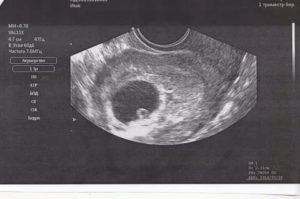

Начало сокращений сердечной мышцы будущего малыша приходится на срок с 3 до 4 недель и уловить его возможно только с помощью трансдюсера (специального узкого вагинального датчика). Случается, что врач-узист не может ничего разглядеть в плодном яйце и рекомендует прийти на обследование через 7–14 дней.

Если в 7 акушерских недель в плодном яйце не будет наблюдаться параметров эмбриона и не будет прослушиваться сердечный ритм, ставится предварительный диагноз анэмбрионии – отсутствия эмбриона в плодном яйце. Однако и в этом случае женщине рекомендуется прийти на дополнительное УЗИ спустя еще 7 дней.

В норме плодное яйцо имеет овальную форму и темно-серый оттенок. Для полноценного наблюдения за формированием плода на УЗИ измеряют следующие показатели.

| Параметр (мм) | Акушерские недели | |||||

| 4 | 5 | 6 | 7 | 8 | 9 | |

| Внутренний контур диаметра плодного яйца | 10 | 18 | 22 | 24 | 30 | 33 |

| Величина копчико-теменного размера | 2–3 | 4–5 | 7–9 | 11–15 | 16–22 | 23–30 |

На отчетливую видимость плода на мониторе ультразвукового аппарата оказывают влияние многие факторы и, если эмбрион не видно, не стоит паниковать – следует подождать две недели и повторить исследование.